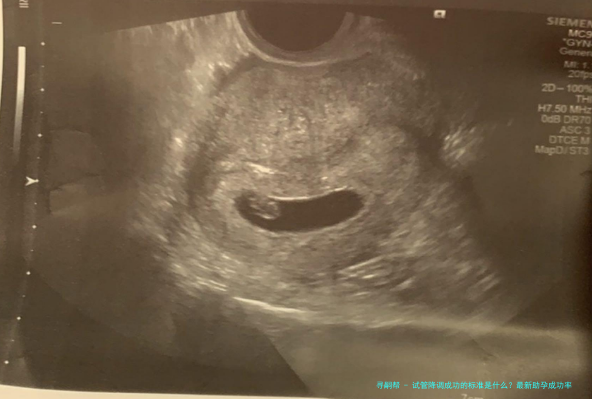

3、B超检查结果

通过B超监测卵巢大小及卵泡成长情形亦是评介降调成效的首要手段其中之一。成功的降调后,可以看到卵巢容积减小,且基础卵泡量数减少或简直消失,说明卵巢活动已得到有效遏止。

4、子宫内膜厚度

理想的降调效果还应该体现在子宫内膜厚度上。通常情况下,降调期间子宫内膜会变得较薄(普通不超越7mm),这有利于随后通过药物推动内膜生长至适宜胚胎移植的情况。